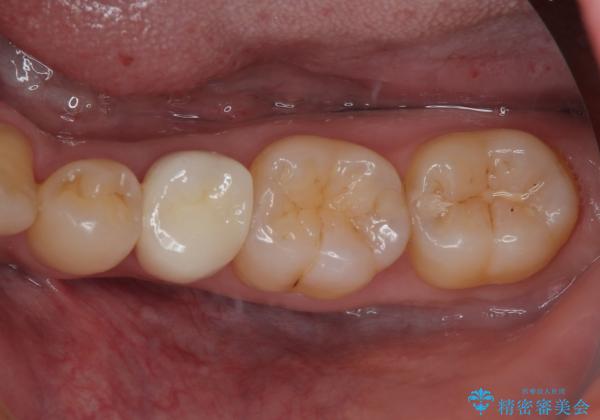

左下にフロスを通すと引っかかる オールセラミッククラウン

- 左下の奥歯のところがフロスが引っかかったり、ちぎれたりするとのことで来院された患者様です。検査の結果、神経は正常な反応を示し、フロスは引っかかる状態でしたので、虫歯治療も併せて行うためにオールセラミッククラウンによる補綴治療を行っていくことにしました。

拡大鏡視野下でプラスチックの詰め物、虫歯を除去しオールセラミッククラウンに適した形に整えました。

フロスがちぎれることもなくなり、被せものが入っていることを忘れていたと大変喜んでいただきました。適合の良い被せものは二次的な虫歯の再発リスクを低減してくれます。